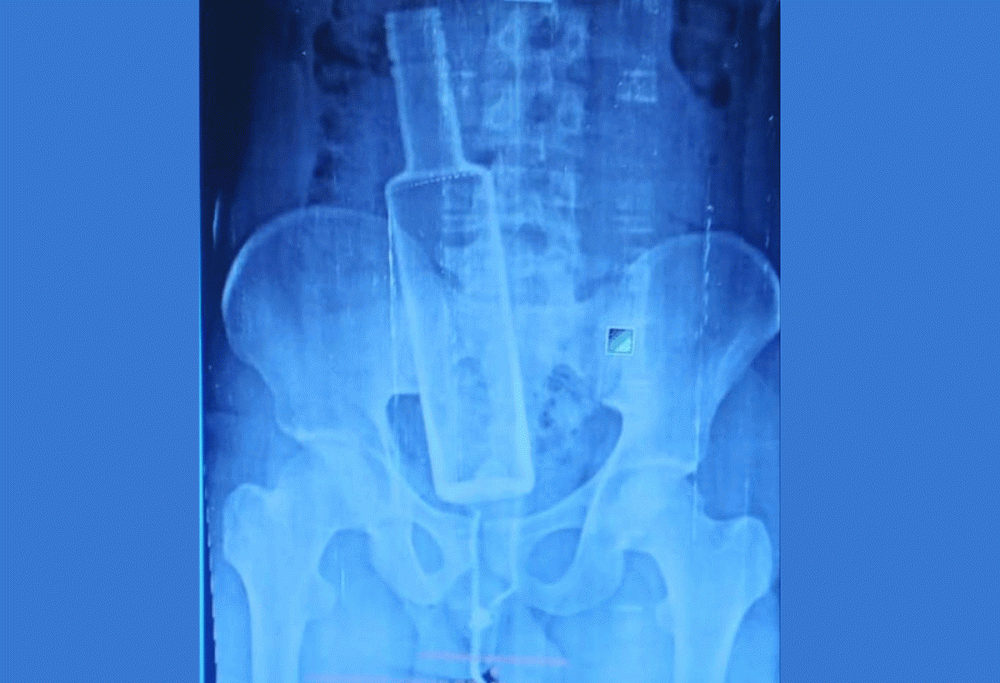

हाल उनी चितवनस्थित पुरानो मेडिकल कलेजको आईसीयूमा चिकित्सकको निगरानीमै छन् । पेट दुखेपछि उपचारका लागि चन्द्रपुर अस्पताल लगिएका नुर्सादको एक्सरे गर्दा पेटमा सिसाको बोतल देखिएपछि थप उपचारका लागि उनलाई चितवनको पुरानो मेडिकल कलेज लगिएको थियो ।

नुर्सादको दिसा पेटभरि फैलिसकेकाले अवस्था अझै जटिल नै रहेको डा। बेलबासेले बताए । मेडिकल कलेजका अनुसार उनलाई अहिले भेन्टिलेटरबाट पोस्ट आईसीयूमा सारिएको छ । आफ्नै साथीले बोतल पेटभित्र पसाइदिएपछि अत्यधिक पेट दुखेर उनलाई उपचारका लागि चन्द्रपुर अस्पताल लगिएको थियो । त्यहाँ पेटको एक्सरे गरेर हेर्दा मात्रै पेटमा सिसाको बोतल रहेको देखिएको थियो ।